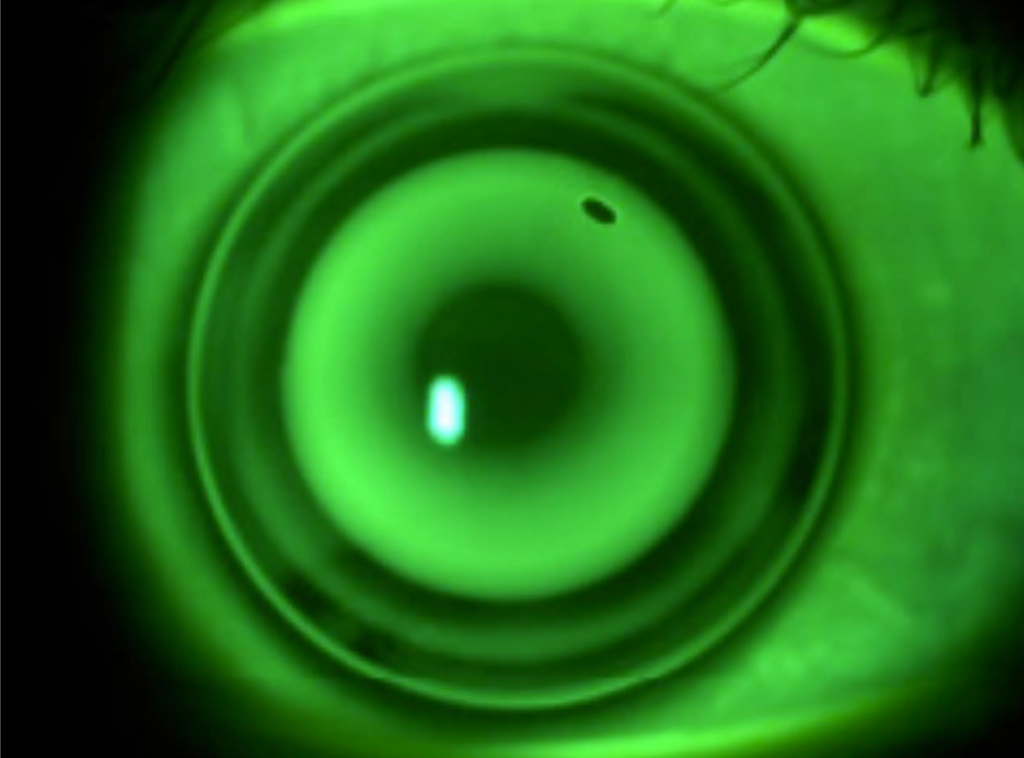

Orto-K

Las lentes Orto-K, también conocidas como “lentes pijama”, moldean suavemente la superficie corneal durante la noche, permitiendo al paciente prescindir de gafas o lentes de contacto durante el día.

El proceso

La ORTO-K es una técnica segura, reversible y sin cirugía que utiliza lentes de contacto especiales mientras duermes. Durante la noche moldean suavemente la córnea para corregir la miopía y otros defectos visuales. Al despertar, disfrutarás de una visión nítida todo el día sin gafas ni lentillas.